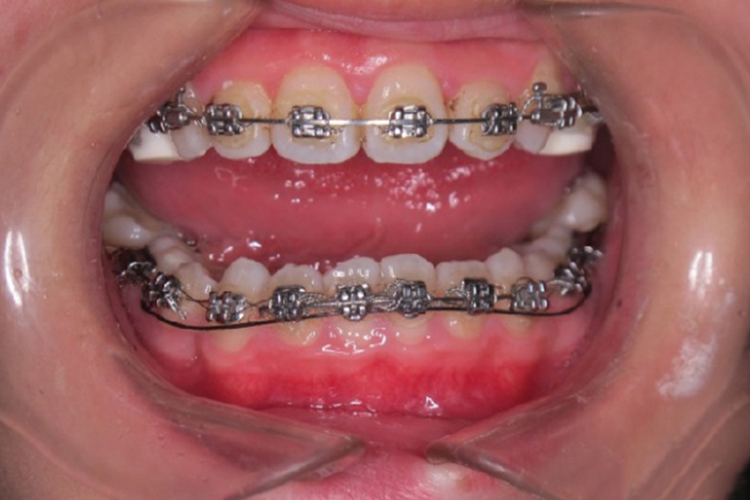

压低辅弓是采用不锈钢丝,通过颊侧附件的口外弓管,沿前庭区域弯一弓形,借助悬吊的力量压低前牙,其反作用力可使磨牙伸高。